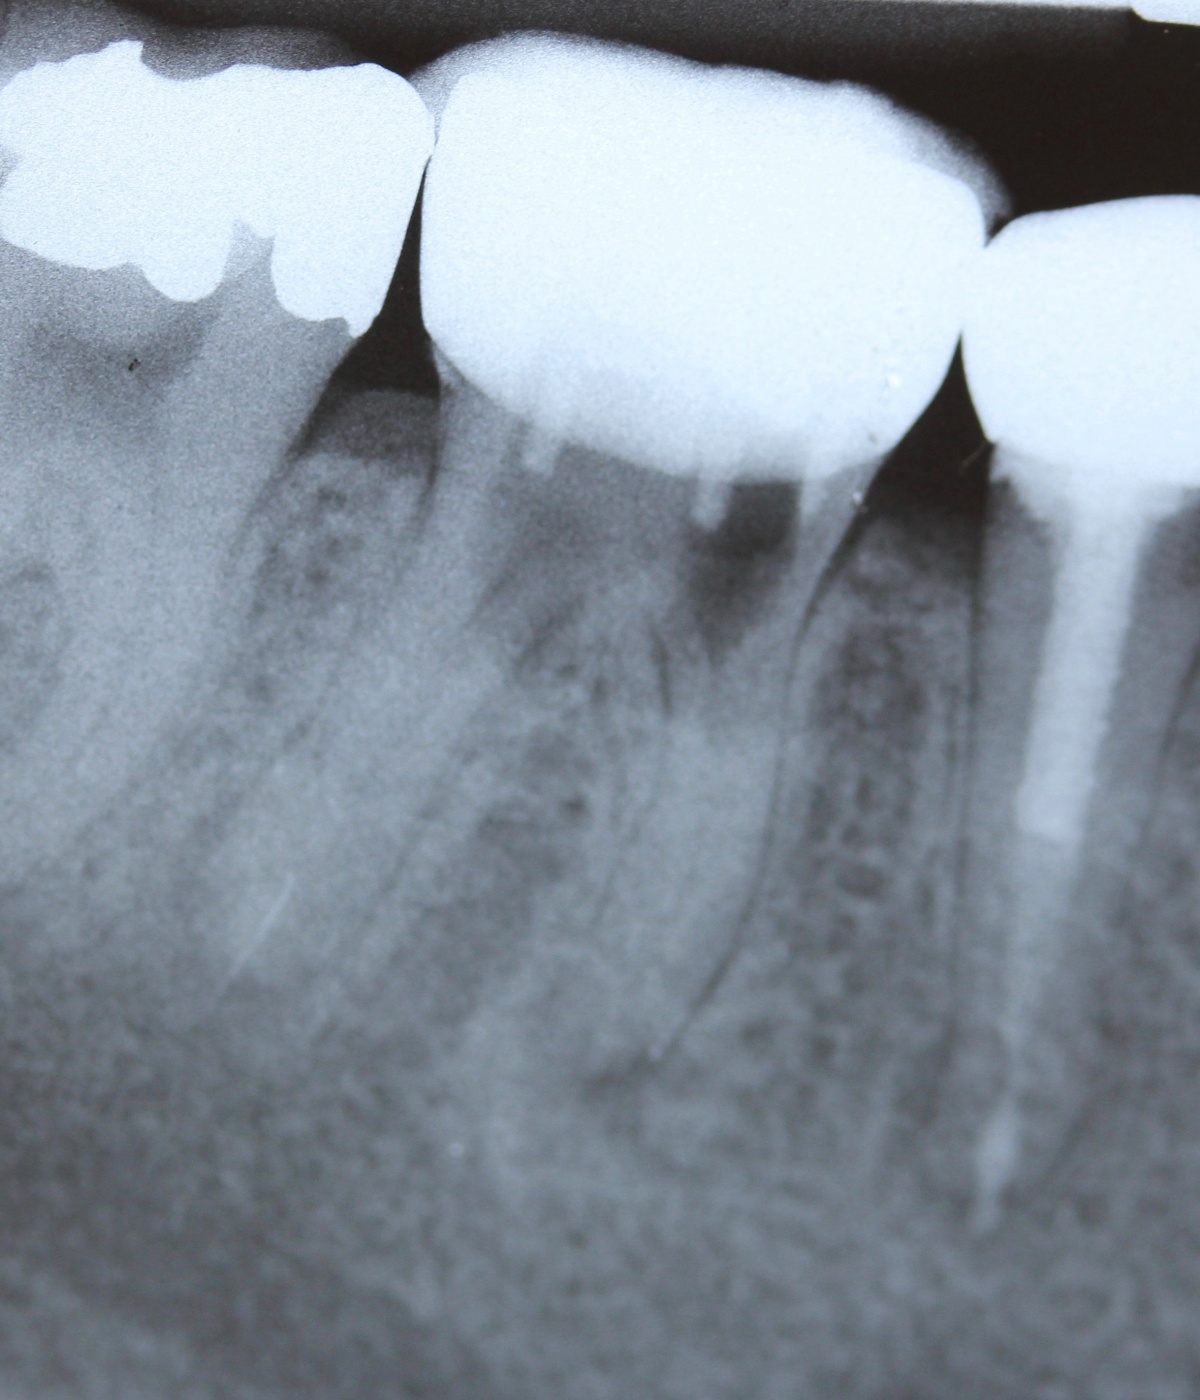

Mit der ansteigenden Zahl der durchgeführten endodontischen Behandlungen steigt proportional auch der Bedarf an Revisionsbehandlungen. Mit einer, abhängig vom Ausgangsbefund, reduzierten Prognose gegenüber der Primärbehandlung bleibt die wiederholte Behandlung des Wurzelkanalsystems in vielen Fällen jedoch klar erste Therapieoption (Abb. 14 und 15).